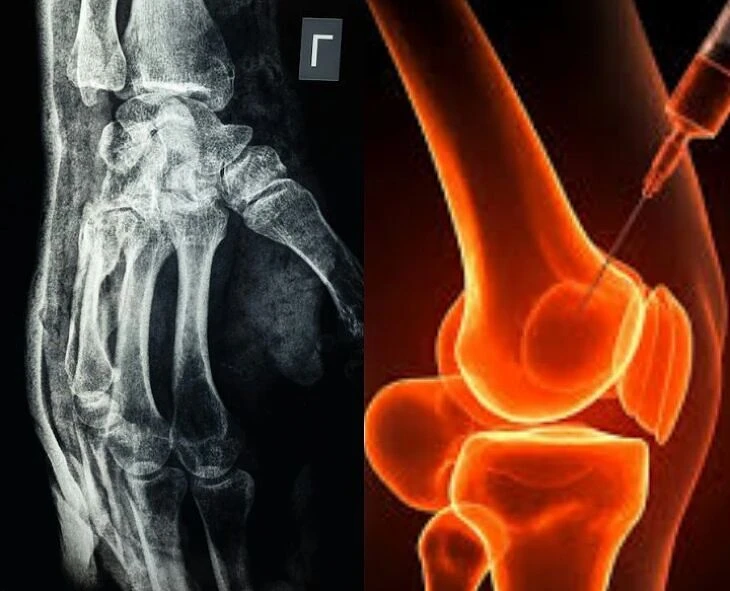

Chinese researchers have discovered a new way to heal broken bones. The glue, called ‘Bone 02’, which can be used to heal broken bones in just 3 minutes, was developed by a team led by Chief Surgeon Lin of Sir Run Run Sha Hospital in Zhejiang Province. They developed it by observing how strongly algae sticks to bridges in water. It was tested on 150 patients and found to work better than traditional methods.